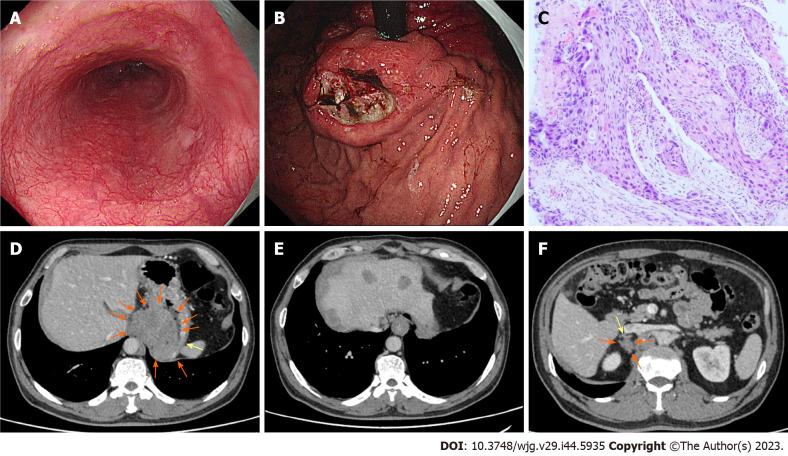

A 56-year-old man was admitted to our hospital because of a dry cough with an esophageal sensation for one year. Endoscopic examination revealed a 2.0 cm 1.0 cm, superficial esophageal squamous cell carcinoma, and the patient underwent endoscopic submucosal dissection (ESD). Fifteen months after ESD, positron emission tomography/computed tomography revealed that the metabolism of the stomach cardia wall had increased slightly. However, the mucosa of the gastric cardia was smooth under gastroendoscopy. Two years after ESD, endoscopic examination revealed a giant gastric cardia carcinoma, while the esophageal mucosa was smooth, and no advanced cancer was found. A biopsy of the gastric cardia indicated squamous-cell carcinoma. The patient received immunochemotherapy and radiotherapy for esophageal cancer for 8 mo and is currently under follow-up.

CONCLUSION

Early-stage esophageal carcinoma with IGM is rare. Despite the ESD of the primary lesion, IGM may still occur and should be closely monitored after ESD.